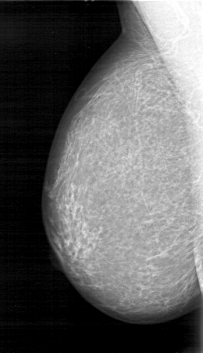

D_4026_1.RIGHT_MLO

RIGHT_CC LINES 5206 PIXELS_PER_LINE 2911 BITS_PER_PIXEL 12 RESOLUTION 43.5 NON_OVERLAY